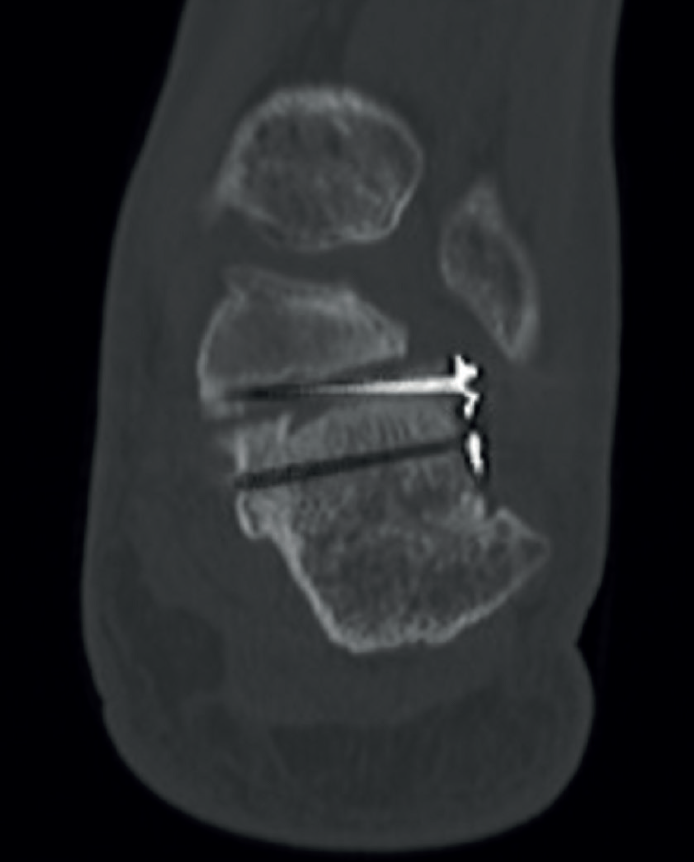

Figura 5. Control de un paciente intervenido por abordaje del seno del tarso con un tornillo intraarticular en mala posición.

Comprobaremos con radioscopia, tanto en las proyecciones lateral como axial (Figura 4), para evitar una mala colocación de los tornillos evitando que se encuentren intraarticulares (Figura 5), el restablecimiento del ángulo de Böhler, la longitud y el varo/valgo del retropié. Tras esta correcta reducción, reducimos la pared lateral previamente levantada y, con un periostotomo pegado al hueso, desperiostizamos el trayecto de los peroneos en dirección posteroinferior y en dirección al proceso anterior, para poder introducir la placa del seno del tarso de forma percutánea (Figura 6).